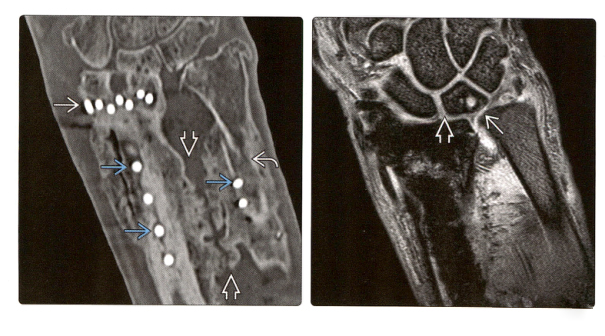

7. (Фото слева) КТ с корональной реконструкцией показывает оссификацию межкостной перепонки после ORIF и перекрестного спондилодеза при лечении оскольчатых внутрисуставных переломов дистального отдела лучевой кости и переломов диафиза локтевой кости. Виден кончик винта.

(Справа) МРТ с корональным градиентным эхо показывает разрыв TFCC и ладьевидно-полулунной связки у этого пациента.